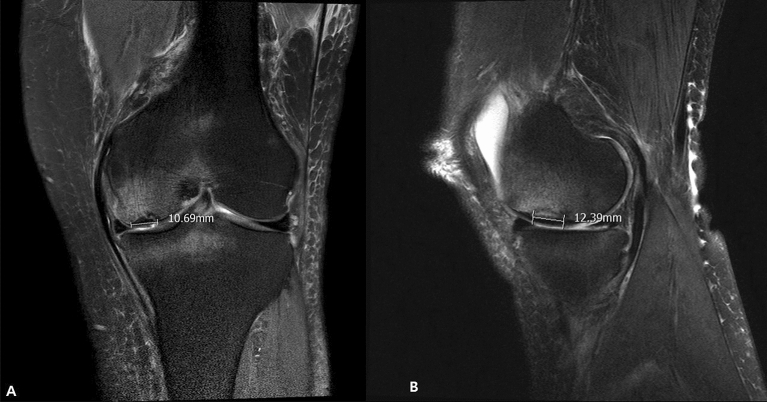

All patients received preoperative MRI scans. MRI characteristics of SIKF include a subchondral area of low signal intensity on T2-weighted images, focal epiphyseal contour depressions, and lines of low signal intensity in the affected condyle19. For the present study, a SIFK lesion was defined as a low signal intensity focus beneath the articular surface in the weight-bearing area of the tibiofemoral compartment on T1-weighted images and a central focal linear subchondral low signal intensity or focal subchondral bone plate impaction with marked surrounding bone marrow edema on fat-suppressed T2-weighted images20 (Fig. 2). The lesion size was measured on coronal and sagittal MR images, and the largest lesion was measured in length (sagittal), width (coronal), depth (deepest portion measured in either coronal or sagittal view)21 (Fig. 3).

Figure 3.

Coronal measurement of the SIFK lesion (left). Sagittal measurement (right). SIFK, subchondral insufficiency fracture of the knee.

No differences in SIFK lesions were found between the TKA and UKA groups. In the TKA group, the average size of lesion was 11.32 mm in width, 17.65 mm in length, and 4.81 mm in depth. The average size of lesion in the UKA group was 13.79 mm in width, 19.62 mm in length, and 5.73 mm in depth (Table 2).